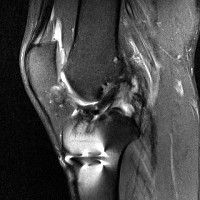

무릎 mri 간단히 봐주실 수 있으시나요 ㅠㅠ

안녕하세요 8년전 십자인대 수술하고 최근 무리한 운동에 무릎 불편감이 생겨서

mri 찍었습니다.

진단결과는 첫 찍은 병원에서 활액막염 이라는 진단을 받았습니다. 혹시 봐주실 수 있으실까요?

진단결과가 달라 혼란스럽습니다 ㅠㅠ

• 안녕하세요. 강성주 의사입니다.

올라온 MRI가 단편적이라서 정확한 진단에 어려움이 있지만 십자인대에는 큰 이상이 있지는 않은것 같으며, 무릎관절내 물이 있는 것으로 보아 활액막염의 진단이 맞을 것 같습니다.

하지만 단편적인 영상이기 때문에 촬영병원에서 정확한 판독지 등을 받으시는 것이 좋겠습니다.